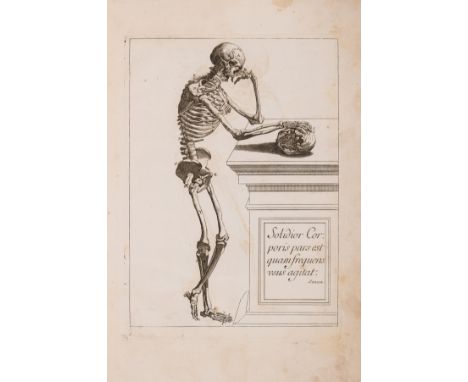

Anatomy.- Tortebat (François) Abregé d'Anatomie, accomodé aux Arts de Peinture et de Sculpture, second edition, engraved pictorial title, 10 engraved full-page illustrations after Vesalius, some spotting and light marginal staining, old marbled wrappers, a little rubbed and stained, spine repaired, preserved in modern cloth folder and slip-case, Paris, J.B.Crepy, 1760; and an Atlas of 13 engraved plates illustrating Scarpa's anatomy (4 with partial hand-colouring), folio (2)⁂ The second most important work on anatomy for the use of artists, first published in 1667 and preceded only by van der Gracht's Anatomie... of 1634. The plates are taken from Vesalius, re-engraved and reversed, and feature male figures as skeletons or displaying their muscles, tendons, etc.